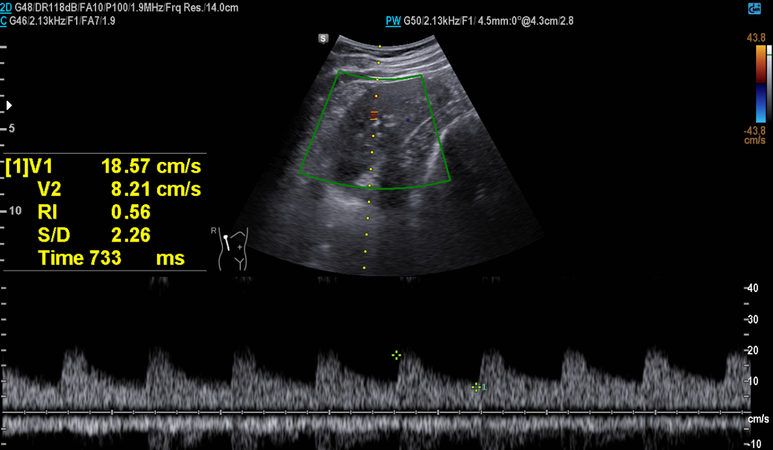

부신 우연종은 없었으며 RI는 정상 범위로 신동맥 협착 배제

부신 우연종은 없었으며 RI는 정상 범위의 상한선 소견, 이외 중등도의 지방간 소견